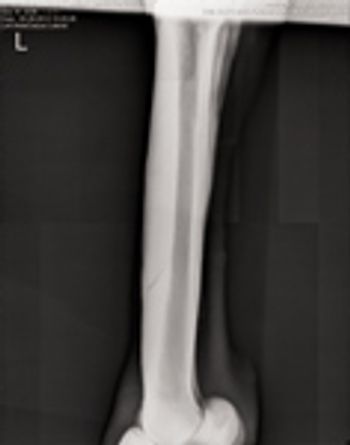

Although fairly prevalent in 2-year-olds, this common inflammatory condition of the cannon bone can affect any Thoroughbred racehorse in training and lead to more serious injury further on in a horse's career.